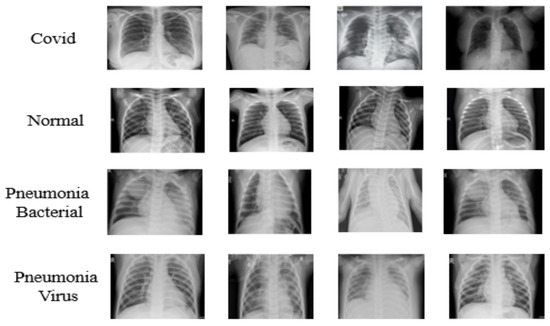

3. Dataset

The COVID-19 dataset [50] utilized in this research [51] was created by Dr. Joseph Cohen, a postdoctoral fellow at the University of Montreal. The Pneumonia [44] dataset Chest X-ray Images was used to build the proposed dataset. The dataset [52] is organized into two folders (train, test) and contains sub-folders for each image category (COVID-19/normal/pneumonia bacterial/ pneumonia virus). There are 306 X-ray images (JPEG) and four categories (COVID-19/normal/pneumonia bacterial/ pneumonia virus). The number of images for each class is presented in Table 3. Figure 3 illustrates samples of images used for this research. Figure 4 also illustrates that there is a lot of variation of image sizes and features that may reflect on the accuracy of the proposed model which will be presented in the next section.

Figure 3. Samples of the used images in this research.